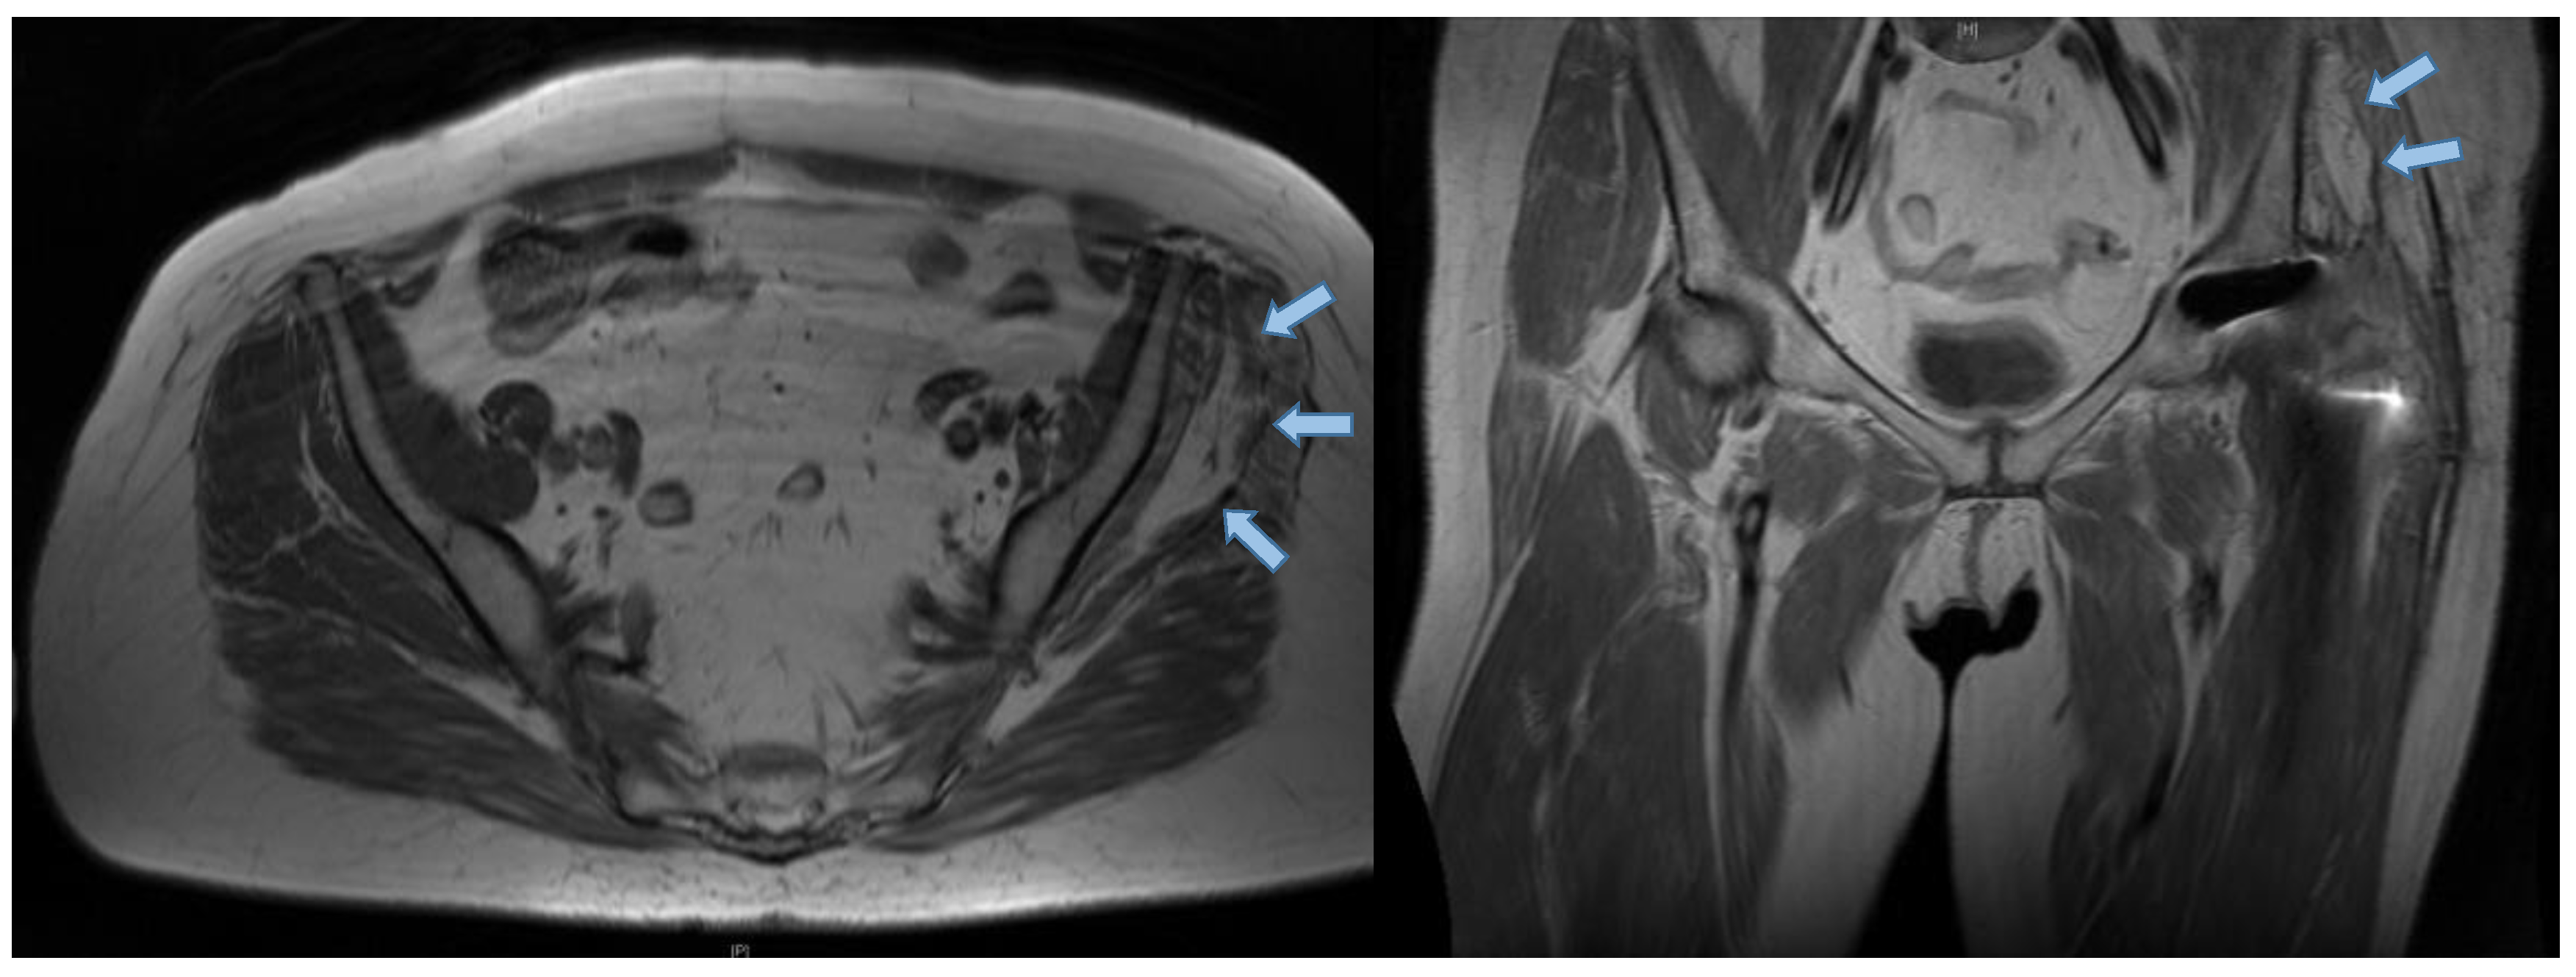

3.3. Radiographic Results